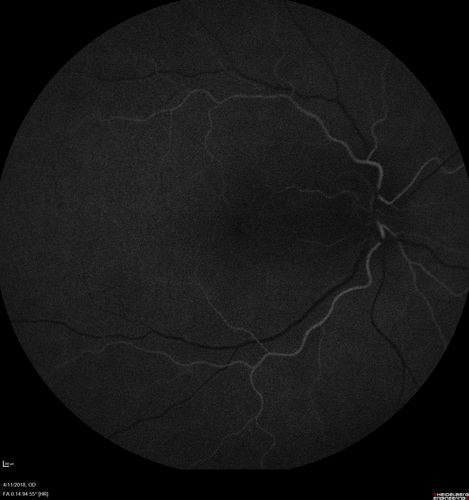

Neuroretinitis - Negative cat scratch serology twice - Possible Behcets

65 year old man with no direct cat exposure and vision loss from neuroretinitis.  His work up was positive for HLA B51.  He had negative cat scratch titers twice.  Vision dropped from 20/60 - 20/200 and then improved to 20/40 over 2 months